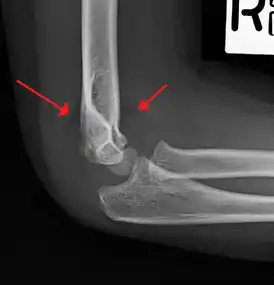

Supracondylar humerus fracture

An elbow X-ray showing a displaced supracondylar fracture in a young child

A supracondylar humerus fracture is a fracture of the distal humerus just above the elbow joint. The fracture is usually transverse or oblique and above the medial and lateral condyles and epicondyles. This fracture pattern is relatively rare in adults, but is the most common type of elbow fracture in children.[1] In children, many of these fractures are non-displaced and can be treated with casting. Some are angulated or displaced and are best treated with surgery. In children, most of these fractures can be treated effectively with expectation for full recovery.[2] Some of these injuries can be complicated by poor healing or by associated blood vessel or nerve injuries with serious complications.

A supracondylar humerus facture is diagnosed by x-ray and the injured limb will be examined to assess the surrounding soft tissue, neurovascular status, and to identify any other injuries to the affected area.[5] Pain, swelling, and deformity near the elbow or arm area is common and a bleed near the fracture may result in an effusion in the elbow joint. With severe displacement, there may be an anterior dimple from the proximal bone end trapped within the biceps muscle. The skin is usually intact. If there is a laceration that communicates with the fracture site, it is an open fracture, which increases infection risk. For fractures with significant displacement, the bone end can be trapped within the biceps muscle with resulting tension producing an indentation to the skin, which is called a "pucker sign".